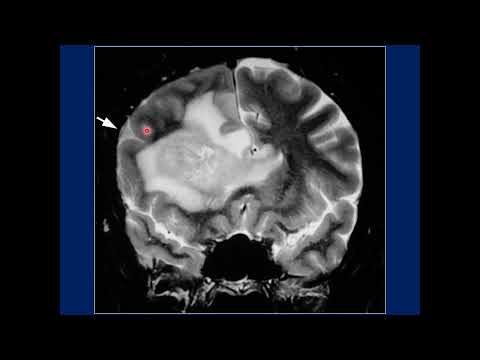

Hellow guys, Welcome to my website, and you are watching Transsulcal Resection Technique for a Cluster of Parietal Cavernous Malformations. and this vIdeo is uploaded by Barrow Neurological Institute at 2022-06-28T16:07:10-07:00. We are pramote this video only for entertainment and educational perpose only. So, I hop you like our website.